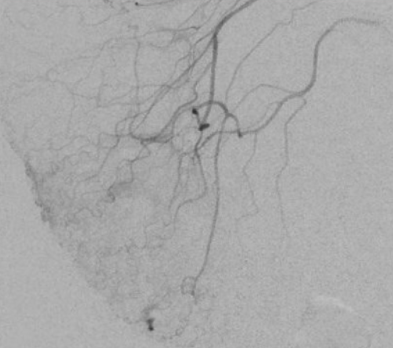

- Prise de contraste focale

- Saignement endoluminal

- Remplissage précoce de la veine antimésentérique (shunt)